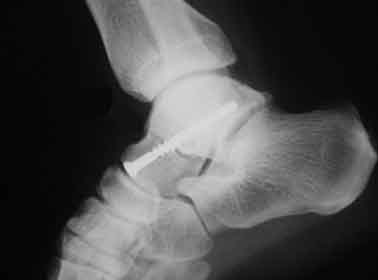

발의 관절이 안쪽으로 강하게 뒤틀어지면 발목과 연결된 거골에 밀려 내과골절이 발생할 수 있고, 뼈가 어긋남 없이 골절되었다면 깁스 등의 보존적 치료등을 하게 됩니다. 하지만, 골절부위가 어긋난 버린 상태라면 스크루핀 등으로 고정하는 수술을 할 가능성이 있습니다.

교통사고등에서 주로 보이는 골절입니다. 이 골절의 특징으로서 혈류장애에 의해 뼈의 괴사를 일으킬 수 있다고 알려져 있어 주의가 필요합니다. 골절부의 어긋남이 없다면 깁스 등의 보존적 치료로 가능하고, 어긋남이 있다면 스크루 등을 이용하여 수술을 할 가능성이 있습니다.